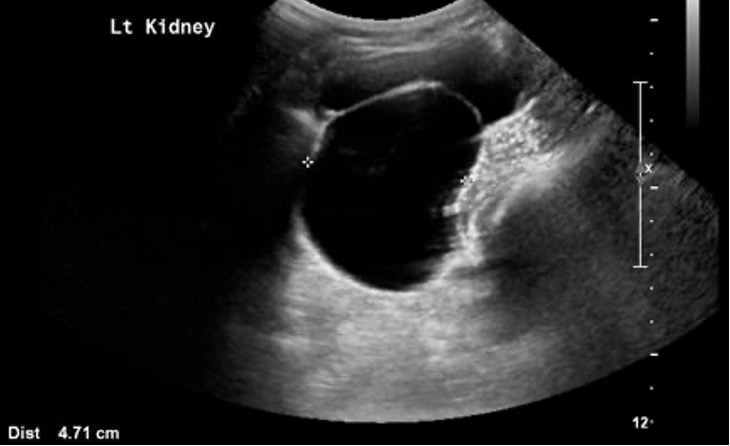

this term describes dilatation of the renal collecting system

What is hydronephrosis?

this obstructive disease grade is called the "bear-claw effect"

What is Grade II?